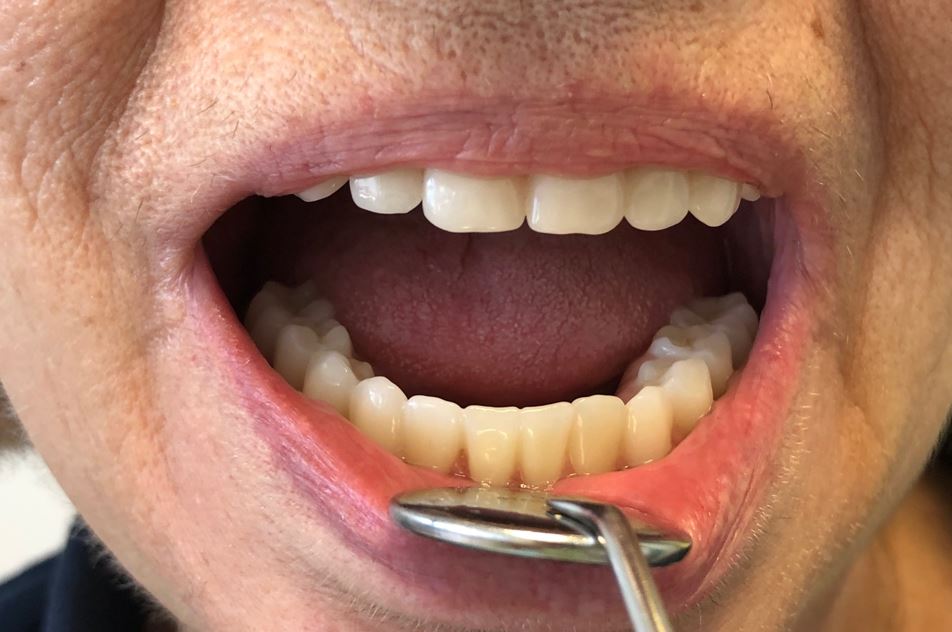

IMPLANTOLOGIA

Nesta área da cirurgia, procedemos à substituição dos dentes perdidos através de implantes dentários certificados. Realizamos cirurgias guiadas, minimamente invasivas, para garantir um maior conforto do paciente.

PRÓTESES

Dispomos de especialistas em reabilitação oral estética, com o objetivo de reproduzir a sua dentição natural, através de próteses fixas (coroas, pontes e facetas dentárias) ou removíveis (esqueléticas ou acrílicas, totais ou parciais).